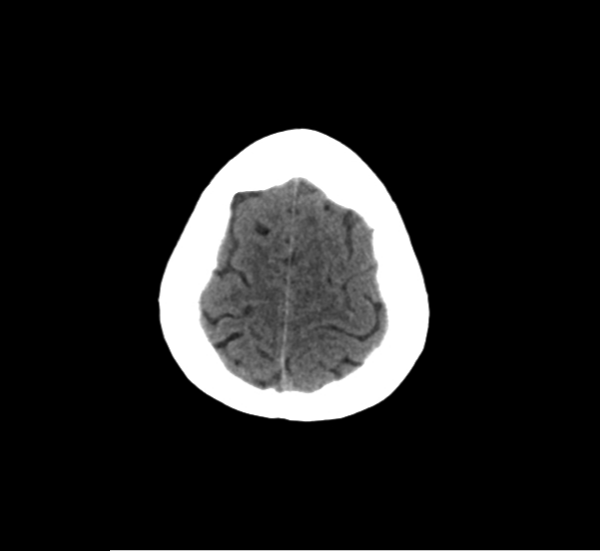

CT Brain Anatomy